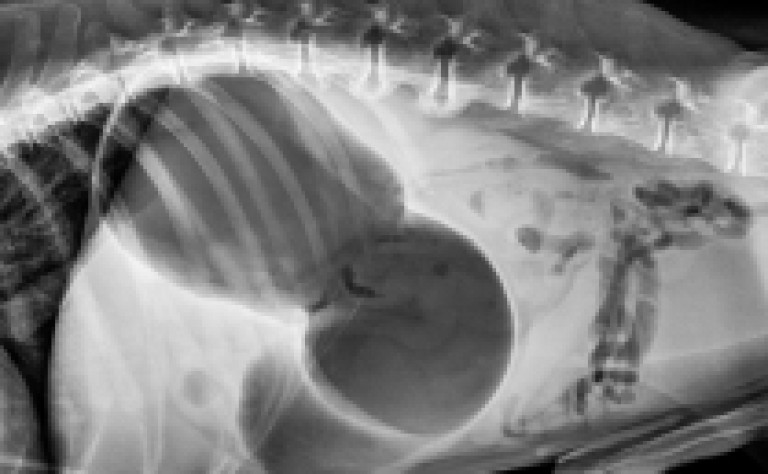

Finalement, le STDE est confirmé ou non grâce à une radio.

La torsion de l’estomac se produit lorsque l’estomac d’un chien se remplit de gaz, de fluide ou d'aliments et se tord sur lui-même.

Lors de la dilatation, l'estomac peut occuper plus de la moitié de la cavité abdominale !

Comme si votre chien avait avalé un gros ballon.

La dilatation est très douloureuse et perturbe le fonctionnement des fonctions vitales telles que la respiration et la circulation du sang.

La torsion du tractus digestif empêche non seulement le gaz de s'échapper, mais il coupe également la circulation sanguine vers certains tissus.